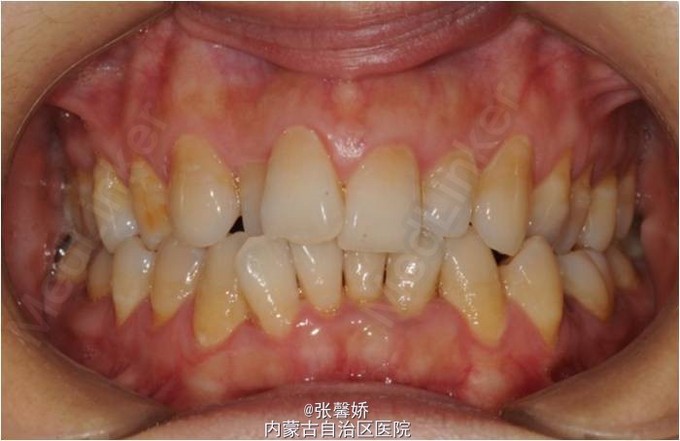

查体 辅查

上中线右偏1mm,A2、D4反合,A2、B2畸形牙偏小,拥挤度上颌4mm、下颌6mm。Spee曲线:左侧3mm,右侧2.5mm

诊断 处理

牙列中度拥挤;A2、D4反合 处理:时代天使隐形矫治器矫治 拔除C8、D8 适当下前牙邻面去釉 排齐整平上下牙列,改正A2、D4反合 治疗时间2年左右,矫治后牙齿排列整齐,咬合关系良好,患者满意。